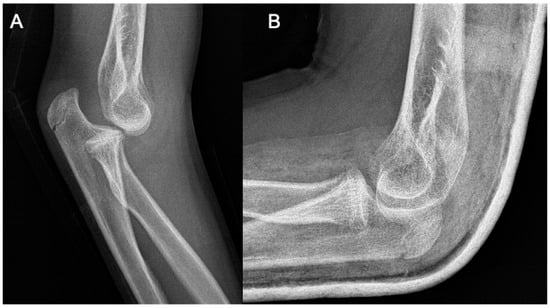

An 11-year-old girl reported to our infirmary on the 10 October 2020 with recurrent posterior subluxation of the elbow. The patient’s history described a previous injury in 2017 when she jumped from a swing and ended up injuring her left elbow (Figure 1). This luxation injury was reduced and treated conservatively with a cast for six weeks. In 2018, she suffered another injury on the same extremity, which was treated the same way. In April 2019, her elbow dislocated three times in a single day, so a cast was applied for seven weeks, and X-rays and CT scans were performed.

Figure 1.

Plain radiographs taken at the initial injury.

In 2020, her elbow dislocated once again when she was climbing onto her bed. In 2020, on the 1 October, she suffered a fall after she was pushed during a sports activity but had only pain and no dislocation, so she received a splint. A few days later, on the 7 October, spontaneous subluxation of the elbow occurred while the child was getting dressed. We applied a dorsal cast to prevent the extremity from suffering further dislocations and planned further static and dynamic diagnostic tests to evaluate the cause of the recurrent dislocations, as the root cause could not be identified on the initial CT or X-ray images that were provided in 2019 (Figure 2).

Figure 2.

CT images were provided for surgical planning; the defect can be seen highlighted in the pink circle.